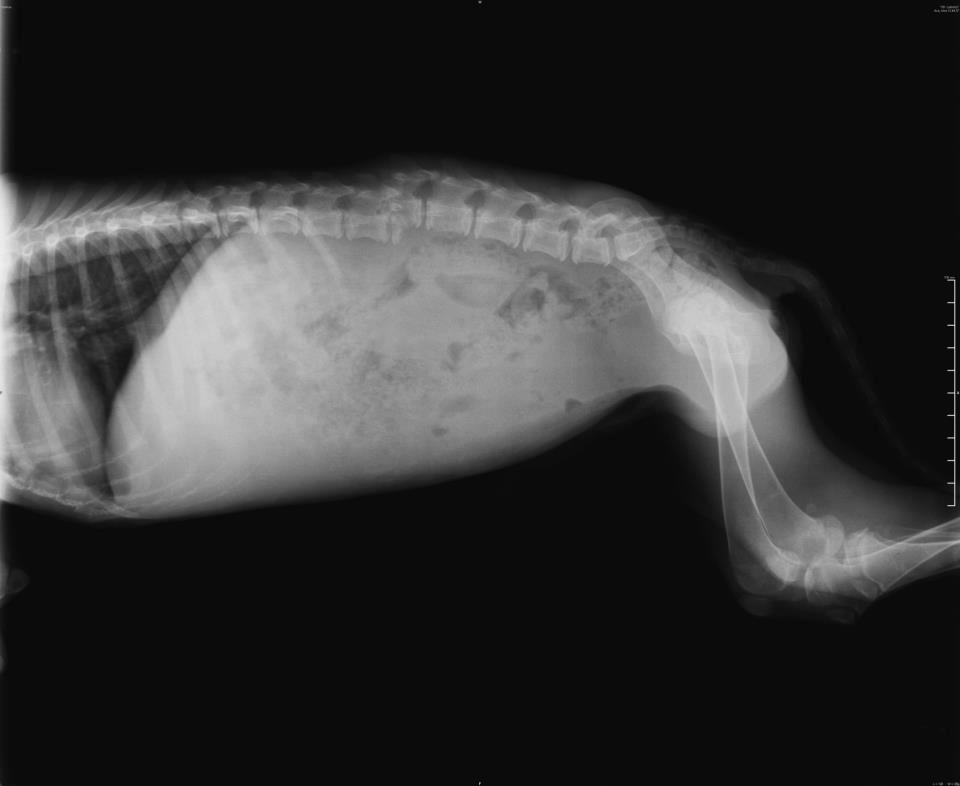

- Joshua’s X-rays 19 March